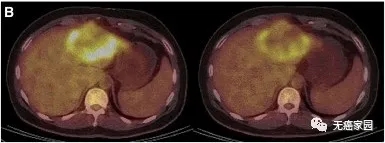

典型病例示意图

患者P9的PET/CT显示肿瘤活性明显减弱